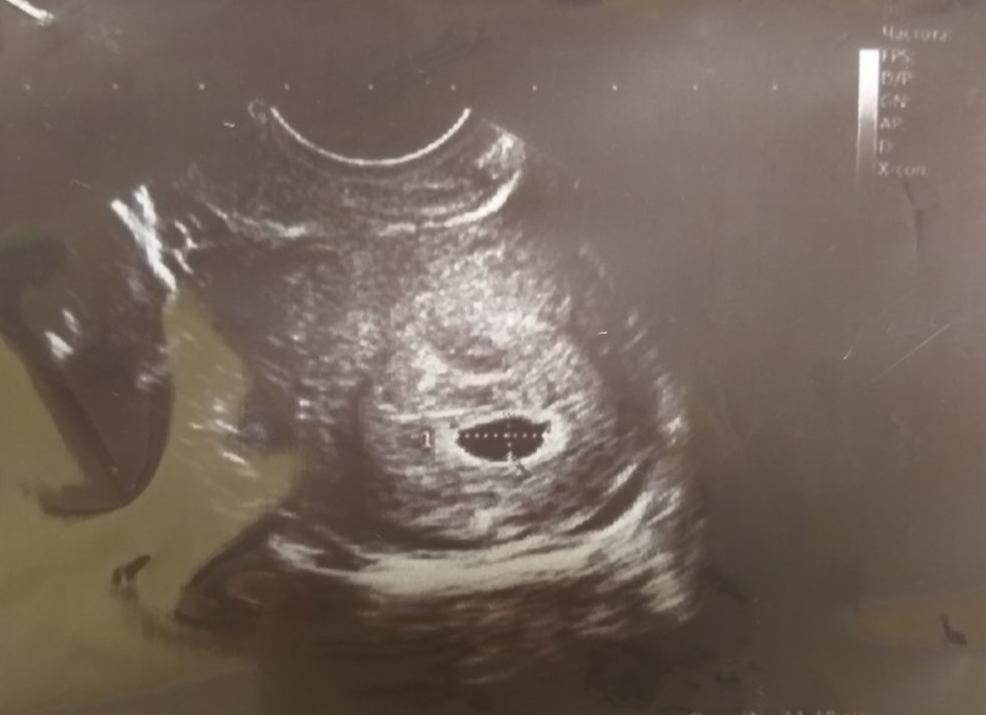

Беременность без эмбриона принято называть анэмбрионией. В этом случае плодное яйцо есть, уровень ХГЧ в крови беременной растет, но эмбрион не лоцируется, т.е. врач УЗИ ничего не видит в полости плодного яйца.

Если врач во время ультразвукового исследования сообщает, что видит в полости матки плодное яйцо — женщину можно поздравить, ведь через 9 месяцев она станет мамой. Установить наличие плодного яйца можно уже на 7-9 день задержки менструации.

Плодное яйцо – овальное или круглое тело диаметром в несколько миллиметров. Диаметр плодного яйца замеряется во время первого же УЗИ. Учитывая его размеры, специалист может установить срок беременности. Но в некоторых случаях погрешность в определении составляет 1-1,5 недели. Поэтому врач, пытаясь установить срок, учитывает также показатели копчико-теменного размера.

Ультразвуковую диагностику применяют для отслеживания течения беременности. То, что будущие родители могут на эмбрион смотреть онлайн — скорее приятный побочный эффект процедуры. Но от этого УЗИ не становится менее радостным. Любому родителю, который может на эмбрион посмотреть онлайн, хочется сказать слова благодарности придумавшему этот метод изобретателю. Когда вы своими глазами видите эмбрион растущего плода, начинаете сильнее ощущать приближающееся время родительских забот. Чтобы на эмбрион ребенка смотреть онлайн, стоит лишь вовремя посетить специалиста по УЗИ. Но помните, что на УЗИ могут быть выявлены проблемы, так что будьте готовы ко всему. Довольно распространенная проблема на УЗИ — это когда эмбрион не визуализируется. Иногда врачи используют и другую формулировку — эмбрион не лоцируется.

Если вам говорят, что эмбрион ваш не лоцируется, то это не повод для паники. Вообще, что значит, что эмбрион не лоцирован? Это — когда видно желток и плодное яйцо, но эмбриона при этом не видно. Эмбрион не визуализирован не только в тех случаях, когда его там попросту нет. Вполне возможно, что эмбрион еще не визуализируется, потому что пока для этого слишком рано. Это случается, когда неверно определен срок беременности. Не паникуйте, лучше посоветуйтесь со специалистом.